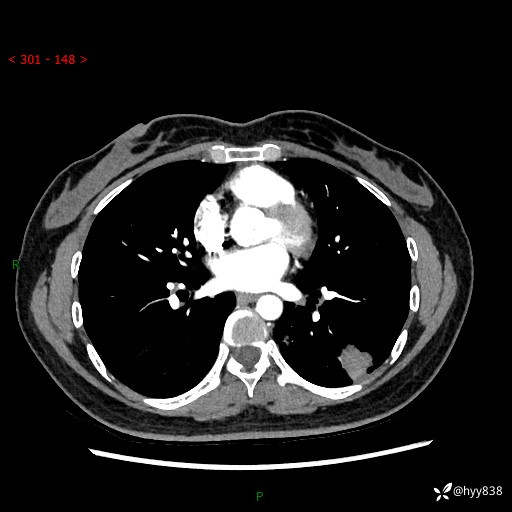

【患者信息】:36岁/女

【主诉】:左侧下胸部阵发性疼痛2周,乏力1周

【现病史及既往史】:患者自诉2周前饮酒后出现左侧下胸部阵发性疼痛,不随呼吸改变,无咳嗽咳痰、头晕头痛、咳血、呼吸困难等不适,于当地第一人民医院查胸部CT提示肺部感染,随后前往我院门诊给予抗感染(左氧氟沙星)治疗1周,自诉胸痛较前好转,感乏力、头晕,偶尔干咳,无咳痰,无发热、畏寒、胸闷、咯血、四肢酸痛、腹泻、腹痛等不适,门诊复查胸部CT提示:左肺下叶感染,病灶较前增加增大,遂以“肺部感染”收入我科。 起病以来,患者精神、饮食、睡眠可,大小便正常,体力体重无明显变化。

【检查】:胸部CT增强(外院平扫)